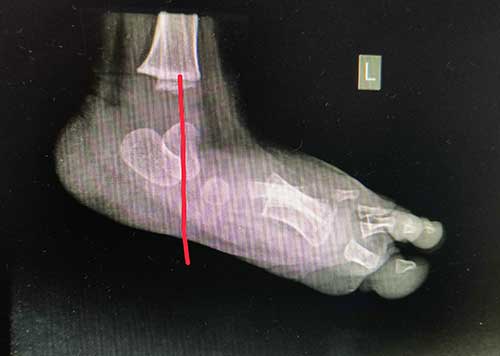

The talus bone is the small bone in the ankle that sits between the tibia and fibula of the lower leg (shin) and the calcaneus (heel bone). The talus connects the lower leg to the foot, and it typically points towards the toes. In a foot with vertical talus, the talus points towards the ground.

With the talus positioned in the wrong direction, the bones that normally form in front of it now sit on top of the talus. The front end of the talus points down towards the sole of the foot and the bones at the end of the foot bend back upward. This results in a stiff foot with no arch that is frequently called a “rocker bottom foot”.

Before treatment